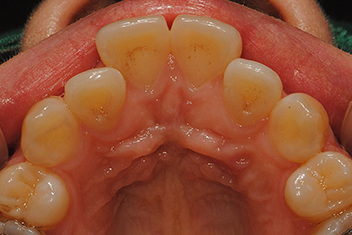

돌출입 개선

치료 기간20개월

상하악 돌출로 인한 돌출입을 투명교정으로 자연스럽게 개선